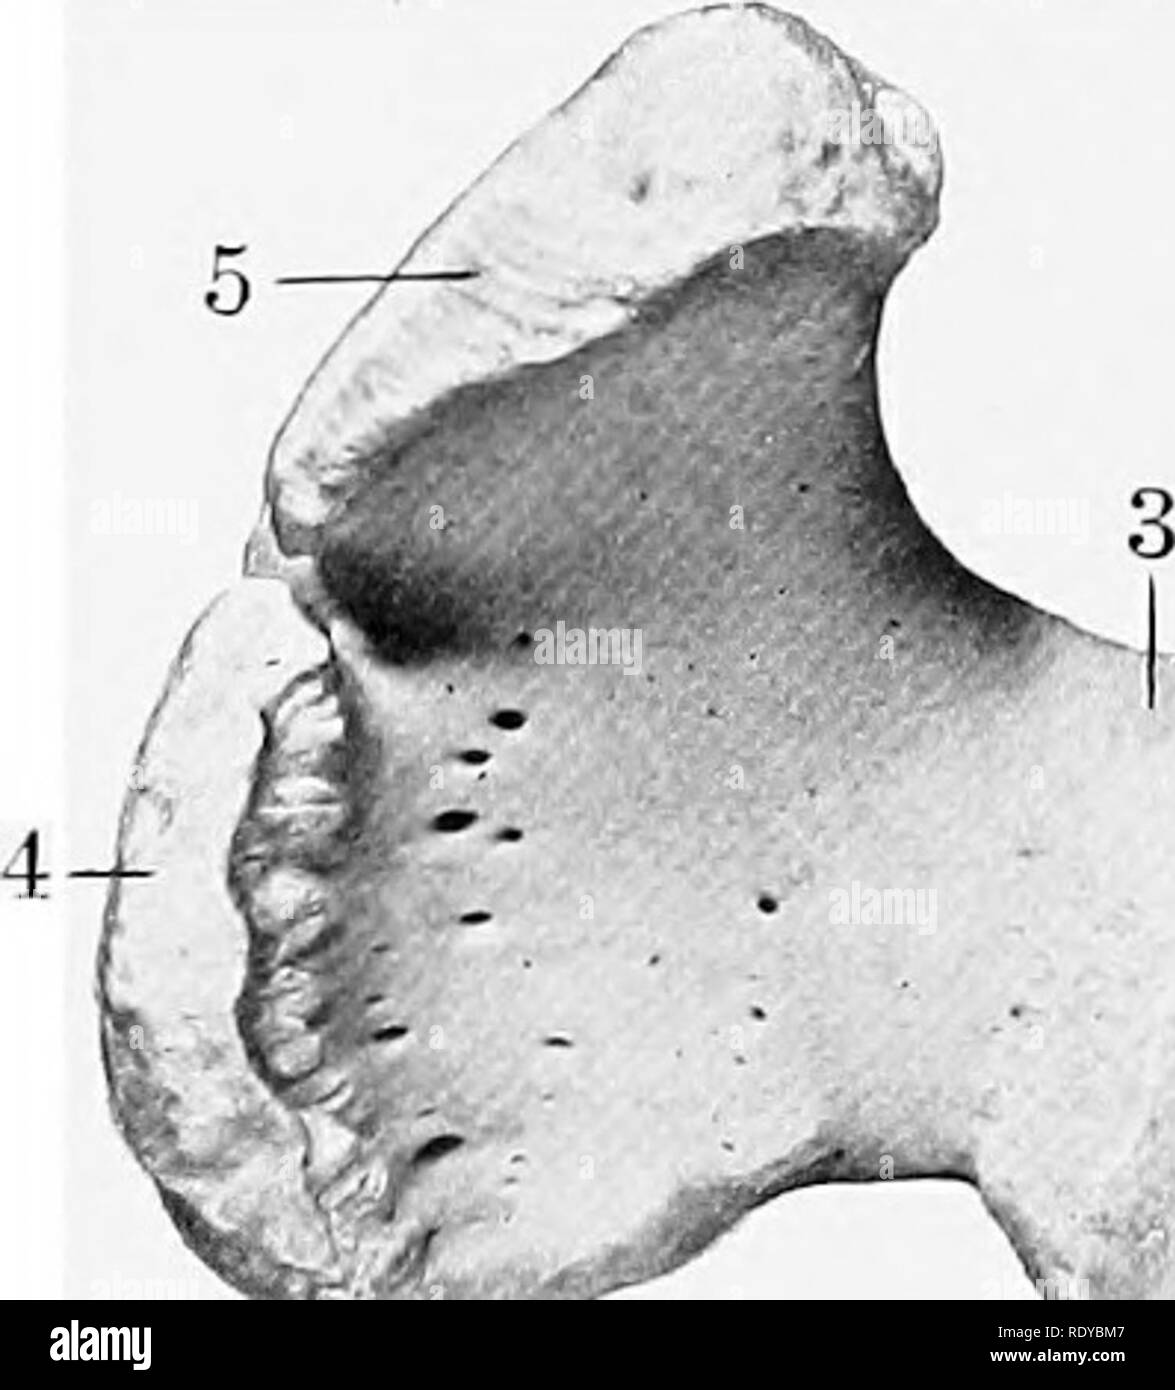

Anatomy the stifle is the equivalent of the human knee and it is the largest most complex joint in the horse. Stifle anatomy radiograph patella femur the equine stifle corresponds to the human knee. The bones that make up the stifle are the femur thigh tibia shin and patella kneecap.

The radiograph at left credit vetwerx is a lateral view of the stifle showing the knee cap or patella and the femur. The stifle is the area where the tibia the bone that forms the gaskin meets the femur the bone that extends upward to the hip.

Communication of the femoropatellar and medial femorotibial joints has been found 60 to 70 of the time although inflammation anatomic variation and unidirectional flow affect this communication. As the leg moves the patella rides up and down the trochlear ridges of the femur in the femoropatellar joint. Observe your horse to see if it holds its leg taut and if it drags the toes of its hoof on the ground behind it.